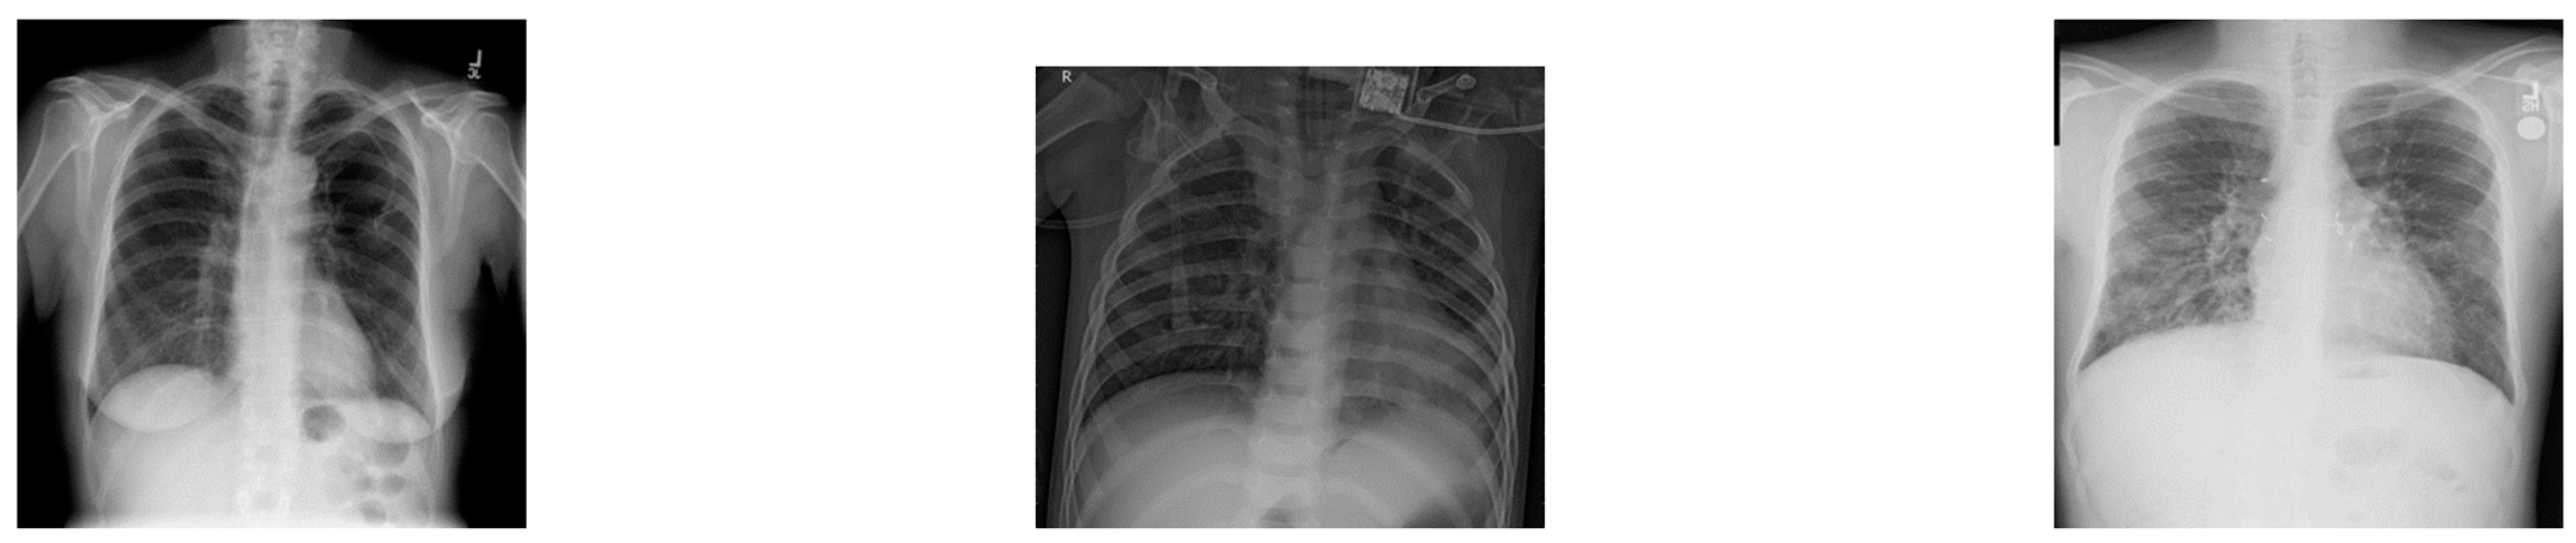

Dataset Visualization